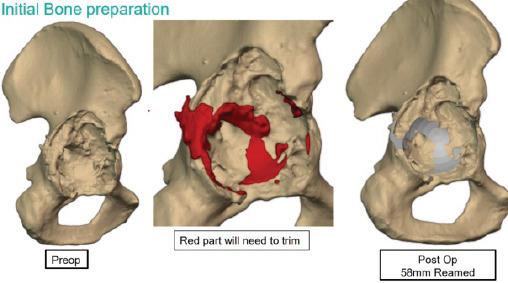

This retrospective case series includes seven patients who underwent revision THA for Paprosky grade 3 acetabular bone loss between January 2023 and April 2024 at two high-volume tertiary care centers. The mean age of the patients was 45 years, with three males and four females included in the study. Pre-operative planning involved advanced imaging techniques, including 3D-computed tomography scans and custom virtual modeling, to design the acetabular components tailored to each patient's specific anatomical requirements.During the surgeries, custom-made 3D-printed titanium augments and cages were used. These implants were fabricated using in-house software, and the turnaround time from the decision to surgery was approximately 10 days. Post-operatively, the planned 3D model was superimposed on post-operative radiographs to assess implant placement accuracy. The Harris hip score at the final follow-up averaged 69.16, with no signs of implant loosening observed.

本回顾性病例系列包括7例患者,他们于2023年1月至2024年4月在两家大型三级医疗中心接受了因Paprosky 3级髋臼骨丢失而进行的翻修全髋关节置换术。患者的平均年龄为45岁,研究纳入了3名男性和4名女性。术前规划涉及先进的成像技术,包括3D计算机断层扫描和定制虚拟建模,以设计适合每个患者特定解剖需求的髋臼组件。在手术过程中,使用了定制的3D打印钛增强物和笼。这些植入物使用内部软件制造,从决定手术到手术的周转时间约为10天。术后,将计划的3D模型叠加在术后X线片上以评估植入物放置的准确性。最后一次随访时的Harris髋关节评分平均为69.16,未观察到植入物松动的迹象。